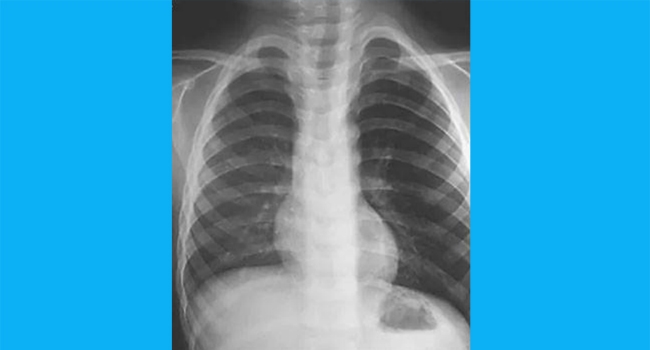

ആഗസ്റ്റ് ഒന്പ്തിനാണ് ഇത്തരത്തില് കുട്ടിയെ ആശുപത്രിയില് പ്രവേശിപ്പിച്ചത്. രണ്ടു ദിവസമായി ഇത്തരത്തില് വ്യത്യസ്ഥമായ ശബ്ദത്തിലാണ് കുട്ടി ചുമയ്ക്കുന്നത് എന്ന് കണ്ടാണ് മാതാപിതാക്കള് കുട്ടിയെ കൊണ്ടുവന്നത്. തുടര്ന്ന് എക്സറെ പരിശോധന നടത്തിയപ്പോള് എന്തോ ഒന്ന് തടഞ്ഞിരിക്കുന്നതായി ശ്രദ്ധയില് പെടുകയായിരുന്നു. ഇത് ശ്വാസമാളത്തിലെ കടുത്ത അണുബാധയ്ക്ക് കാരണമായിരിക്കാമെന്നും ശസ്ത്രക്രിയ നടത്തി പുറത്തെടുക്കുകയും ചെയ്യുകയായിരുന്നു.

കളിപ്പാട്ടത്തില് ഉപയോഗിക്കുന്ന വിസിലാണ് ഇത്തരത്തില് കുടുങ്ങിയിരുന്നത്. എന്നാല് എങ്ങിനെയാണ് കുട്ടിയുടെ ഉള്ളില് ഇത്രയധികം വലിപ്പമുള്ള വിസില് എത്തിയതെന്ന് അറിയില്ല. കുട്ടി ഈ പ്രശ്നങ്ങള്ക്ക് കുറച്ചുനേരം മുന്പ് കളിപ്പാട്ടം വച്ച് കളിച്ചിരുന്നുവെന്നു മാതാപിതാക്കള് പറഞ്ഞു.